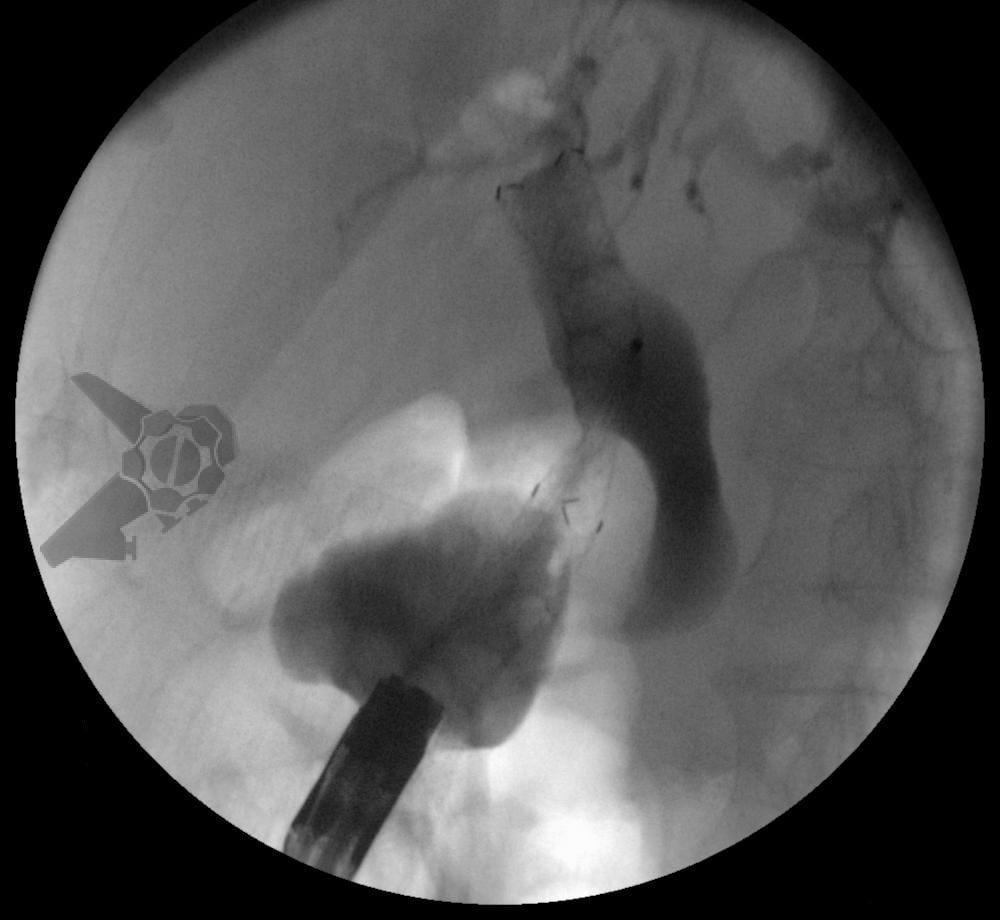

Drenagem biliar ecoguiada (EUS-BD) defini-se pela drenagem utilizando ecoendoscopia para puncionar a via biliar intra ou extra-hepática. Há quatro técnicas descritas: EUS-BD rendezvous, drenagem ecoguiada coledocoduodenal (EUS-CD), drenagem ecoguiada hepatogástrica (EUS-HG) e drenagem anterógrada.

- EUS-CD: drenagem ecoguiada com prótese da via biliar extra-hepática através da janela bulbar, conectando a via biliar extra-hepática e o duodeno

- EUS-HG: drenagem ecoguiada com prótese da via biliar intra-hepática esquerda através da janela gástrica, conectando a via biliar intra-hepática esquerda com o estômago